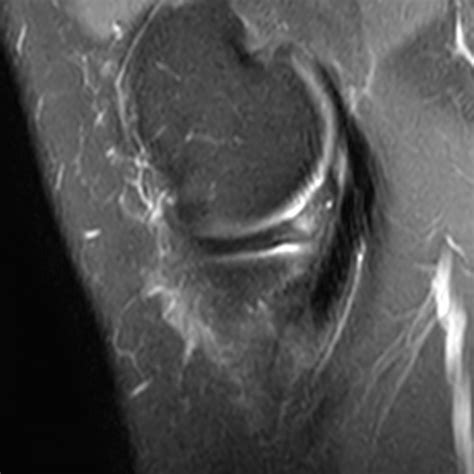

• Magnetic Resonance Imaging (MRI) to provide detailed images of the meniscus and surrounding structures. MRI is particularly useful in identifying the location and extent of the tear.